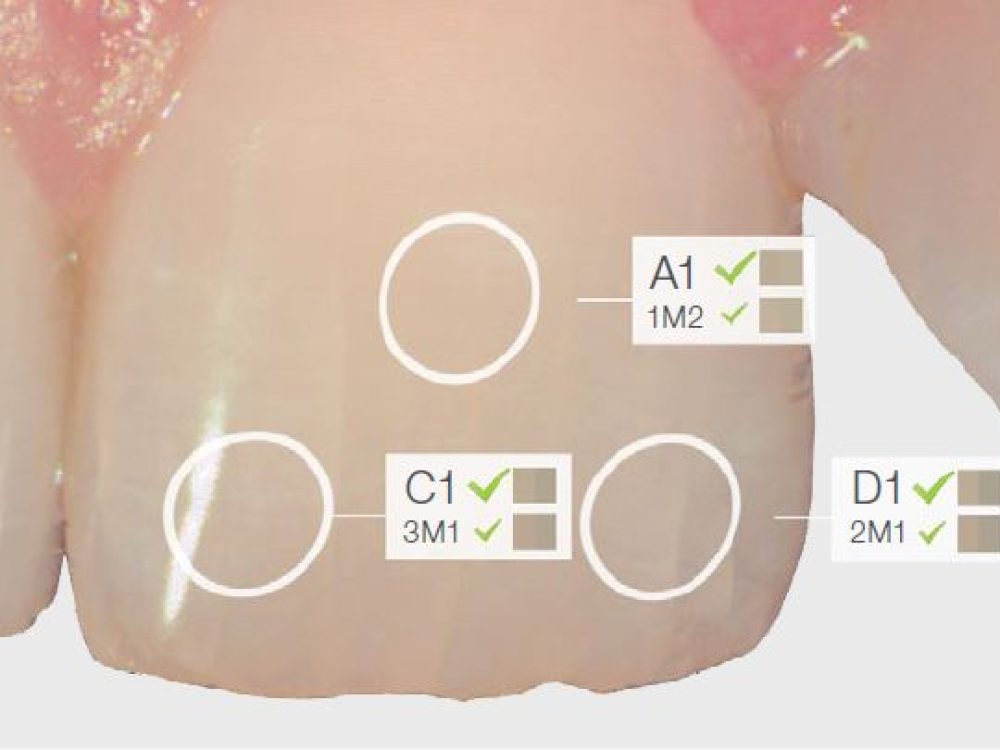

Die neue Generation von TRIOS®, ein digitales System für Abformungen, vereint drei Komponenten: Einen Intraoralscanner für die schnelle und mühelose 3D-Farbabformung, eine integrierte intraorale Kamera und Farbbestimmung beim Scannen für präzisere und besser berechenbare Ergebnisse. TRIOS® ermöglicht Ihnen, effizienter und präziser zu arbeiten und Ihren Patienten mehr Komfort zu bieten. Erfahren Sie in diesem Workshop alle Details über die faszinierenden Möglichkeiten des Full Digitalen